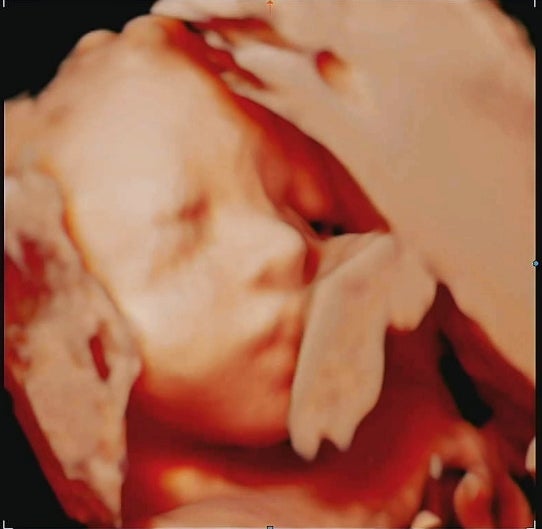

임신 후기 28주차 증상 / 송파고은빛 입체초음파 할인

임신 28주차 자궁수축 이벤트가 있어서그런지 순식간에 찾아온 듯한 임신 28주차. 28주차부터 임신 후기에 ...